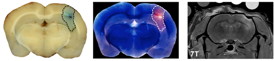

| Pathologic and MRI evidence of blood-brain-barrier (BBB) disruption induced by the VEIN (Vascular Enabled Integrated Nanosecond) pulse generation system. |

Two, minimally invasive needle electrodes with 1 mm active length were spaced 4.0 mm apart and inserted into the right cerebral hemisphere 1.5 mm beneath the surface of the dura. A burst of 200, 500 ns duration square pulses of alternating polarity with a voltage-to-distance ratio of 250 V/cm were applied through the electrodes. In the case shown above, bursts were repeated once per second for 10 min. The extent of BBB disruption is shown by the dotted line surrounding Evans blue-albumin complex uptake on the gross brain slice preparation (left) and the corresponding fluorescent image (middle). Additionally, areas of BBB disruption appear as hyperintense (white) on the T1-weighted MRI exam, due to the uptake of a gadolinium-Evans blue tracer. Scale bar represents 5 mm. (Credit: John H. Rossmeisl Jr., Neurology and Neurosurgery, Virginia-Maryland Regional College of Veterinary Medicine and Virginia Tech-Wake Forest University School of Biomedical Engineering and Sciences).